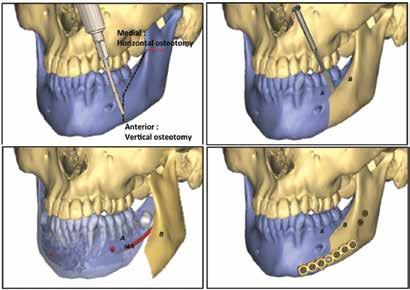

91 “Split to save”: Accessing mandibular lesions using sagittal split osteotomy with virtual surgical planning

Stanley Yung-Chuan Liu, MD, DDS; Douglas Sidell, MD; Leh-Kiong Huon, MD; Carlos Torre, MD